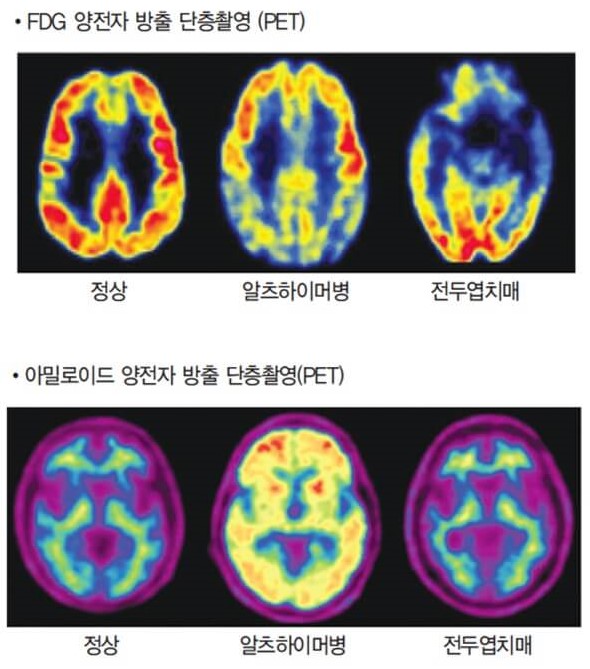

방사선 동위원소를 이용하여 뇌의 혈류량 또는 뇌의 포도당 대사능력 등을 측정함으로써 뇌의 각 부위의 기능이상을 확인할 수 있다. 양전자방출단층촬영(PET), 단일광자방출단층촬영(SPECT) 등이 여기에 속한다. 뇌의 각 부위의 기능 이상을 확인할 수 있어 알츠하이머병, 혈관성 치매, 전두측두엽 치매 등 치매 아형을 감별하는 데 도움이 된다. 또한 구조적 뇌영상 검사에서 이상 소견이 현저하지 않은 초기 알츠하이머병의 경우 뇌기능이 저하 여부를 조기에 발견할 수 있어 치매의 조기잔단에 유용하다. 초기 알츠하이머병의 경우, FDG-PET로 포도당 대사의 감소를 확인할 수 있고 아밀로이드 PET 검사에서 뇌 속 아밀로이드 베타의 축적을 확인할 수 있다.